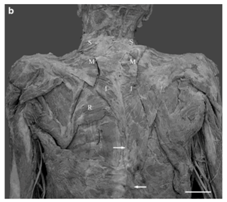

Emsley et al.12 have reported a morphological anomaly found during a cadaverous dissection on a 89year-old subject. The left trapezius was significantly smaller than the right trapezius, especially in its caudal part. They also noted that the muscle fibers of the left trapezius were much lighter than on the right. Moreover, the existing fibers of the left trapezius inferior to the scapula were only one-third to two-thirds as thick as those on the right. The vertebral attachment of the inferior fibers of the left trapezius was also notably higher than that on the right. Morphometric analysis indicated that the surface area of the left trapezius was approximately 50% that of the right trapezius. In addition, the orientation of the fibers was different (Figure 2).

Figure 3 A: Digitized image of a unilaterally hypoplastic trapezius muscle on the left side.

B: Arrows indicate the approximate inferior attachment points of the left and right trapezius muscles. Note the easily visible rhomboideus major muscle (R) on the leftside. Superior (S), middle (M), and inferior (I) segments of trapezius. Scale bar 5 cm [12].